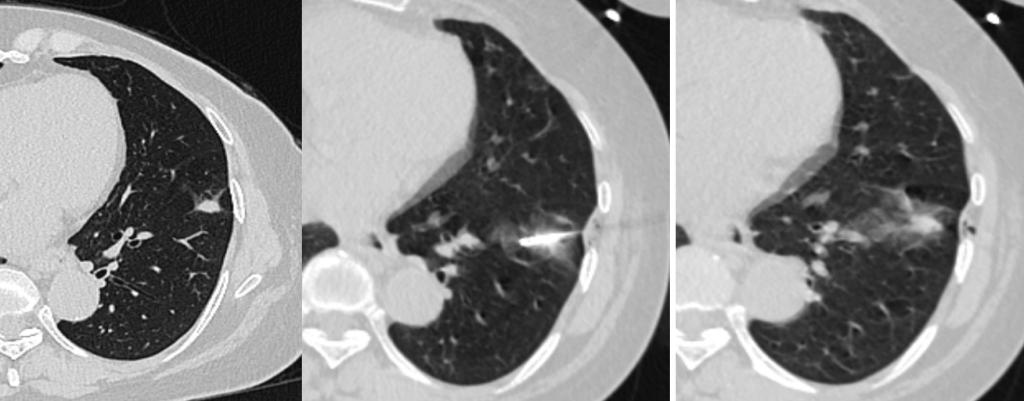

行射频消融术的患者是一名61岁的女性,2年前曾行肝内胆管癌切除术,此次入院肺部CT提示左肺下叶内基底段一大小约12*8mm高密度结节,较前对比明显增大,考虑肺转移瘤。胸外科与医学影像科专家团队进行深入讨论和综合评估,告知患者及家属具体治疗方案及替代方案后,患者及家属拒绝外科手术,决定选择CT引导下肺肿瘤射频消融术。经过周密的术前准备,医学影像科CT介入团队在CT定位引导下精准穿刺病灶位置,成功实施了射频消融治疗。手术持续约1小时,术中患者耐受良好,术中、术后未见明显出血、气胸、胸腔积液等并发症;术后达到肿瘤消融目标,且患者能即刻下床活动,不影响正常生活。

CT引导下肺结节射频消融术是近年来快速发展起来的一种微创治疗手段,在CT影像定位的精确引导下,将特制的消融电极针精准穿刺插入病灶的核心部位,通过射频电流使病变区域的组织细胞发生高速震荡、摩擦,转化为热能,使肿瘤细胞在高热状态下凝固性坏死,被机体吸收或组织纤维化,实现了不开刀消除实体肿瘤的目的。这一技术尤其适用于直径小于3cm的肺部肿瘤的治疗,疗效确切,可达到根治,且术后恢复快,切口感染几率低,费用相对较低。肺结节射频消融治疗为患者带来了更加精准、安全、高效、个体化的诊疗体验,显著提高了患者的生活质量。